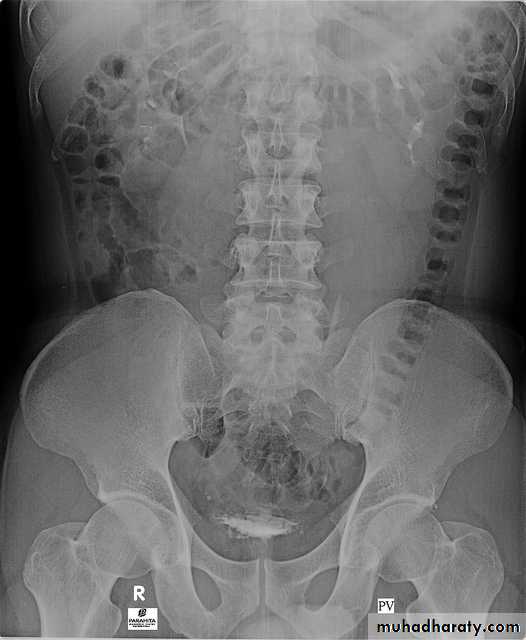

5. A full bladder film (with the urinary bladder fully distended with contrast)

Urinary tract

4. Bladder

The bladder is a centrally located structure.

Smooth in outline.

Smooth indentation from above by uterus on the right or sigmoid colon on the left and from below by muscles of the pelvic floor is normal.

Other than that, any filling defect, wall irregularity or diverticula must be carefully looked for.